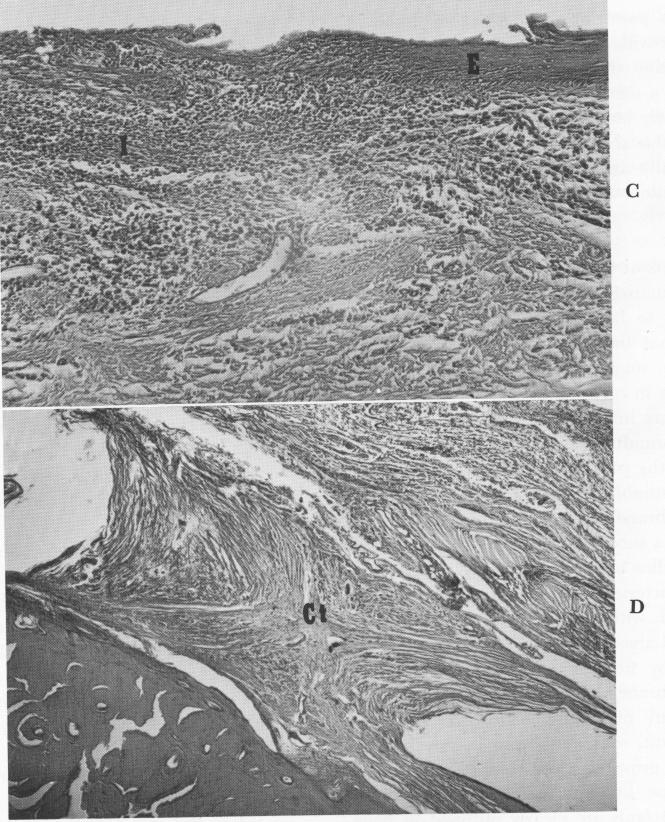

and the bone, was the thickest soft tissue observed in all the sections. An epithelial layer fifteen to twenty cells deep lined its surface, and the underlying connective tissue contained inflammatory cells that in-creased in number on the buccal and lingual sites of the abutment. The epithelium lining the space occupied by the primary strut decreased until it faded out completely 2 to 3 mm. from the penetration site and was replaced by typical implant connective tissue. At this point, the inflammatory cells accompanying the epithelial invagination increased, suggesting that epithelial invagination along a strut is related to inflammation. Considering the small amount of invagination over a 12-year period, the findings are most significant and encouraging.

The connective tissue adjoining the buried metal portions was normal and dense. Those layers immediately facing the metal contained flattened, elongated cells that gave those layers a tendon-like character.

1 Nature of epithelial and inflammatory cells near subperiosteal implant site